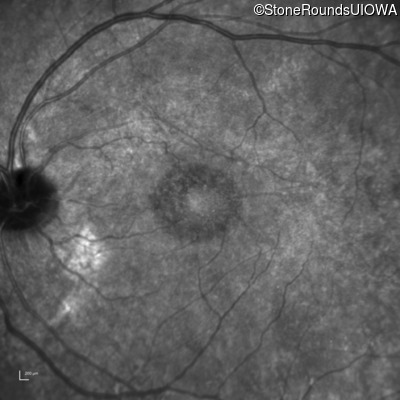

This 44 year old man became photophobic about 6 years ago. He has been taking Imuran since his kidney transplant 23 years ago.

| Senior-Loken Syndrome | NPHP1 | Gly343Arg G(GG)>A(GG) | Deletion of Entire Gene | AR |